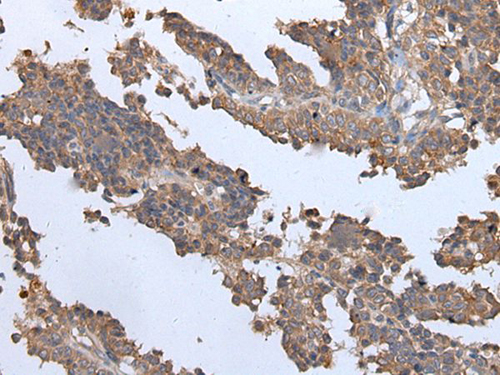

IHC (Immunohistochemistry)

(The image on the left is immunohistochemistry of paraffin-embedded Human ovarian cancer tissue using ENPP2 Antibody at dilution 1/35, on the right is treated with synthetic peptide. (Original magnification: x200))